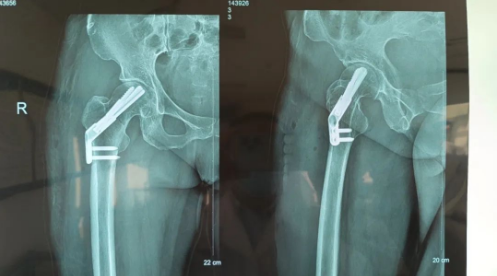

经过周密的手术准备后,创伤科李培龙主任带领团队为患者实施了微创FNS内固定保髋手术。手术前使用闭合手法复位,复位后透视见正侧位片复位满意,安装FNS内固定系统,手术用时40分钟,切口大小只有4厘米。手术创伤及时间比传统内固定手术大大减少,手术过程不对骨折周围血供产生干扰,最大可能地降低股骨头坏死的几率。术后影像学检查显示骨折对位对线良好,内固定稳定可靠。

患者FNS术后影像